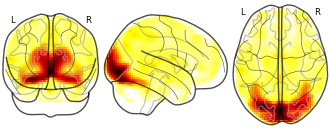

"description": "Multi-modal analysis in BPD. Brain regions exhibiting smaller gray matter and decreased activation during emotion processing in BPD compared to healthy controls. Note: Results were thresholded at p<.0025. Note2: Results were updated (see Erratum for this publication).",